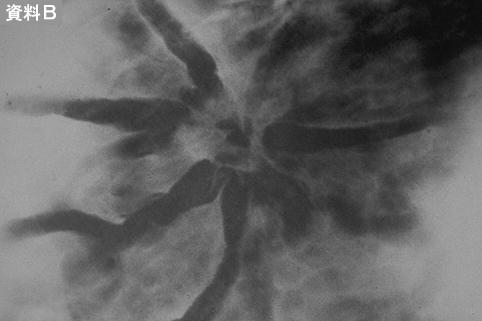

[Image-ID:12171]

검사방법 기타